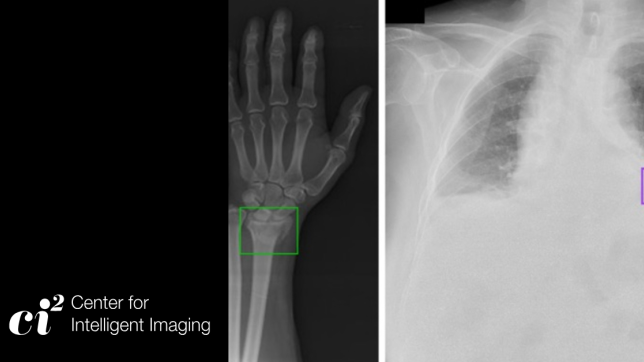

The Center for Intelligent Imaging (ci2) is based in UCSF’s Department of Radiology and Biomedical Imaging and is comprised of clinical radiologists, imaging scientists, engineers, machine learning scientists, data engineers, clinicians, post-doctoral fellows and students

The Center’s dedicated focus on medical imaging by leveraging the power of data -- access to massive image databases, its extensive annotated image archives, and domain knowledge at all organ and disease levels positions it to lead in the discovery, innovation and translation of intelligent imaging.